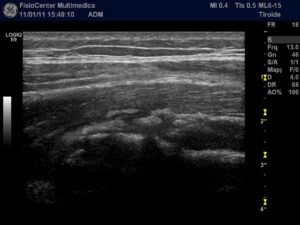

28.12.2010

In corrispondenza del terzo prossimale del muscolo retto femorale di destra si osserva area anecogena a margini netti che misura 44,3 mm. in scansione longitudinale.

Quadro compatibile con versamento, verosimilmente ematico, secondario a trauma contusivo diretto.

11.01.2011

In corrispondenza del terzo prossimale del muscolo retto femorale di destra si osserva completa risoluzione del versamento precedentemente riscontrato.

Si consiglia ripresa sportiva graduale (idrokinesiterapia, esercizi isometrici e poi training concentrico/eccentrico).